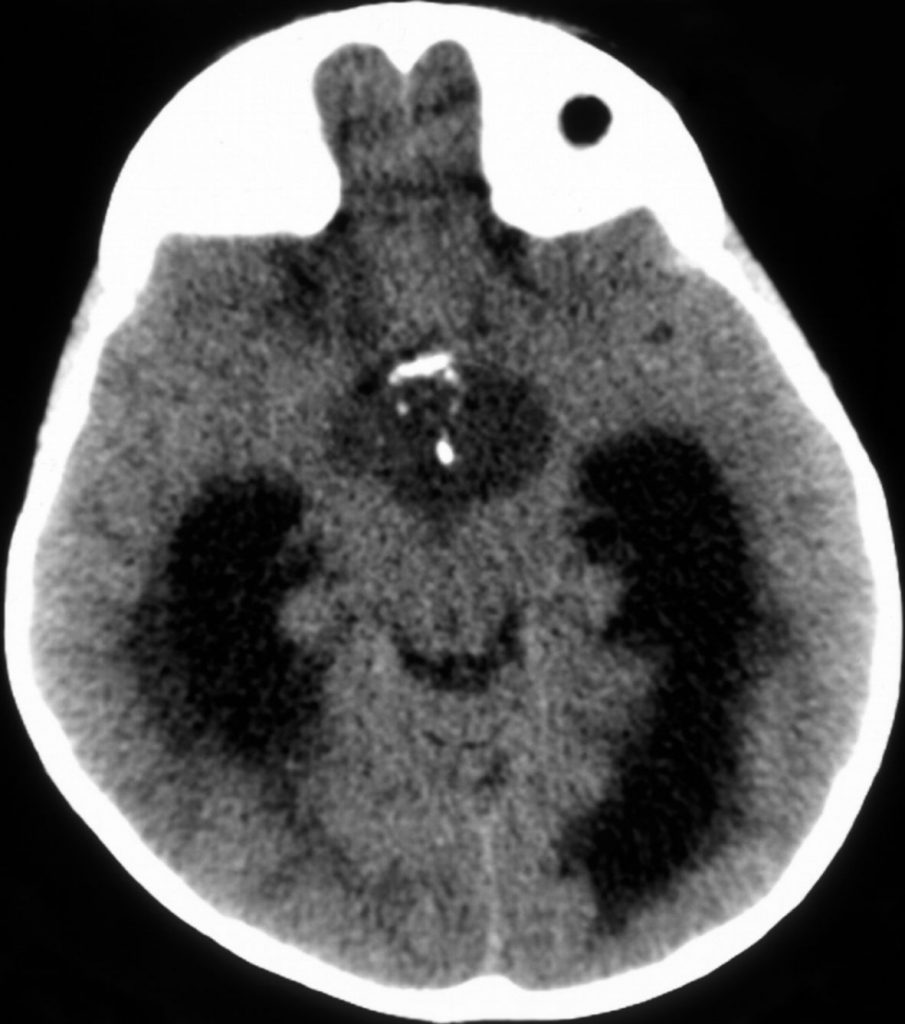

A. Tomodensitométrie cérébrale

La TDM montre classiquement un syndrome de masse dans la selle turcique et/ou suprasellaire, associant typiquement des calcifications, des lésions kystiques et des lésions tissulaires (figure 112.1). En cas d’hydrocéphalie, il existe une dilatation ventriculaire avec des plages d’hypodensités périventriculaires, correspondant à des troubles de résorption transépendymaire du liquide cérébrospinal.

Fig. 112.1 Tomodensitométrie cérébrale. Craniopharyngiome.

Masse kystique calcifiée. Dilatation des cornes temporales des ventricules latéraux avec hypodensités périventriculaires traduisant une hydrocéphalie.

Source : CERF, CNEBMN, 2022.